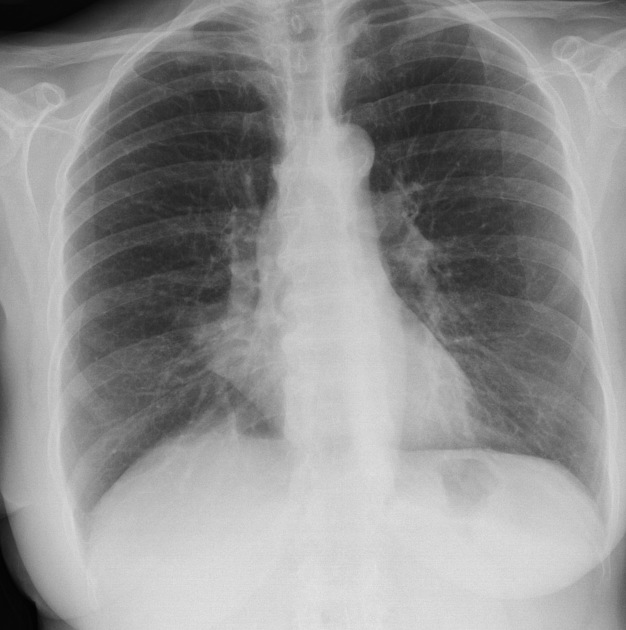

lobar lung collapse pacs

from pacs.de